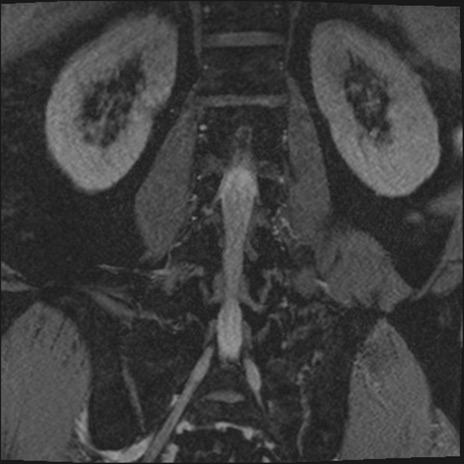

【整形】TIPS症例2 腰椎MRI 3D(冠状断像)

【症例】70歳代男性

【主訴】左下肢痛

【現病歴】2週間前くらいから腰痛、左下肢痛あり。左臀部から大腿、下腿外側のしびれが常時ある。歩行とともに同部位の痛みあり。

【身体所見】Lasegue70-/60+、Bragard-/±、PTR ±/±、ATR -/-、IP 5/5、TA 5/4、TS 5/5、EHL 右第1足趾なし/3、FHL 5/5、hypersthesia(-)、足背動脈触知良好

異常所見と診断は?